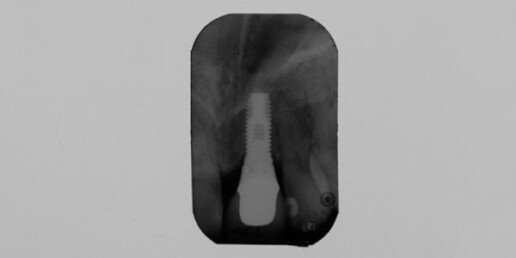

Implantologia computer guidata

Caso 1

Un software progetta la chirurgia, da cui viene ricavata una mascherina. Gli impianti vengono inseriti senza tagli, senza suture, senza sanguinamento, con il carico immediato dei denti in giornata. Questa tecnica necessita di una buona conoscenza dei mezzi informatici e chirurgici del dentista, semplificando per il paziente l’atto chirurgico, il comfort, il dolore e la riduzione dei tempi operatori.